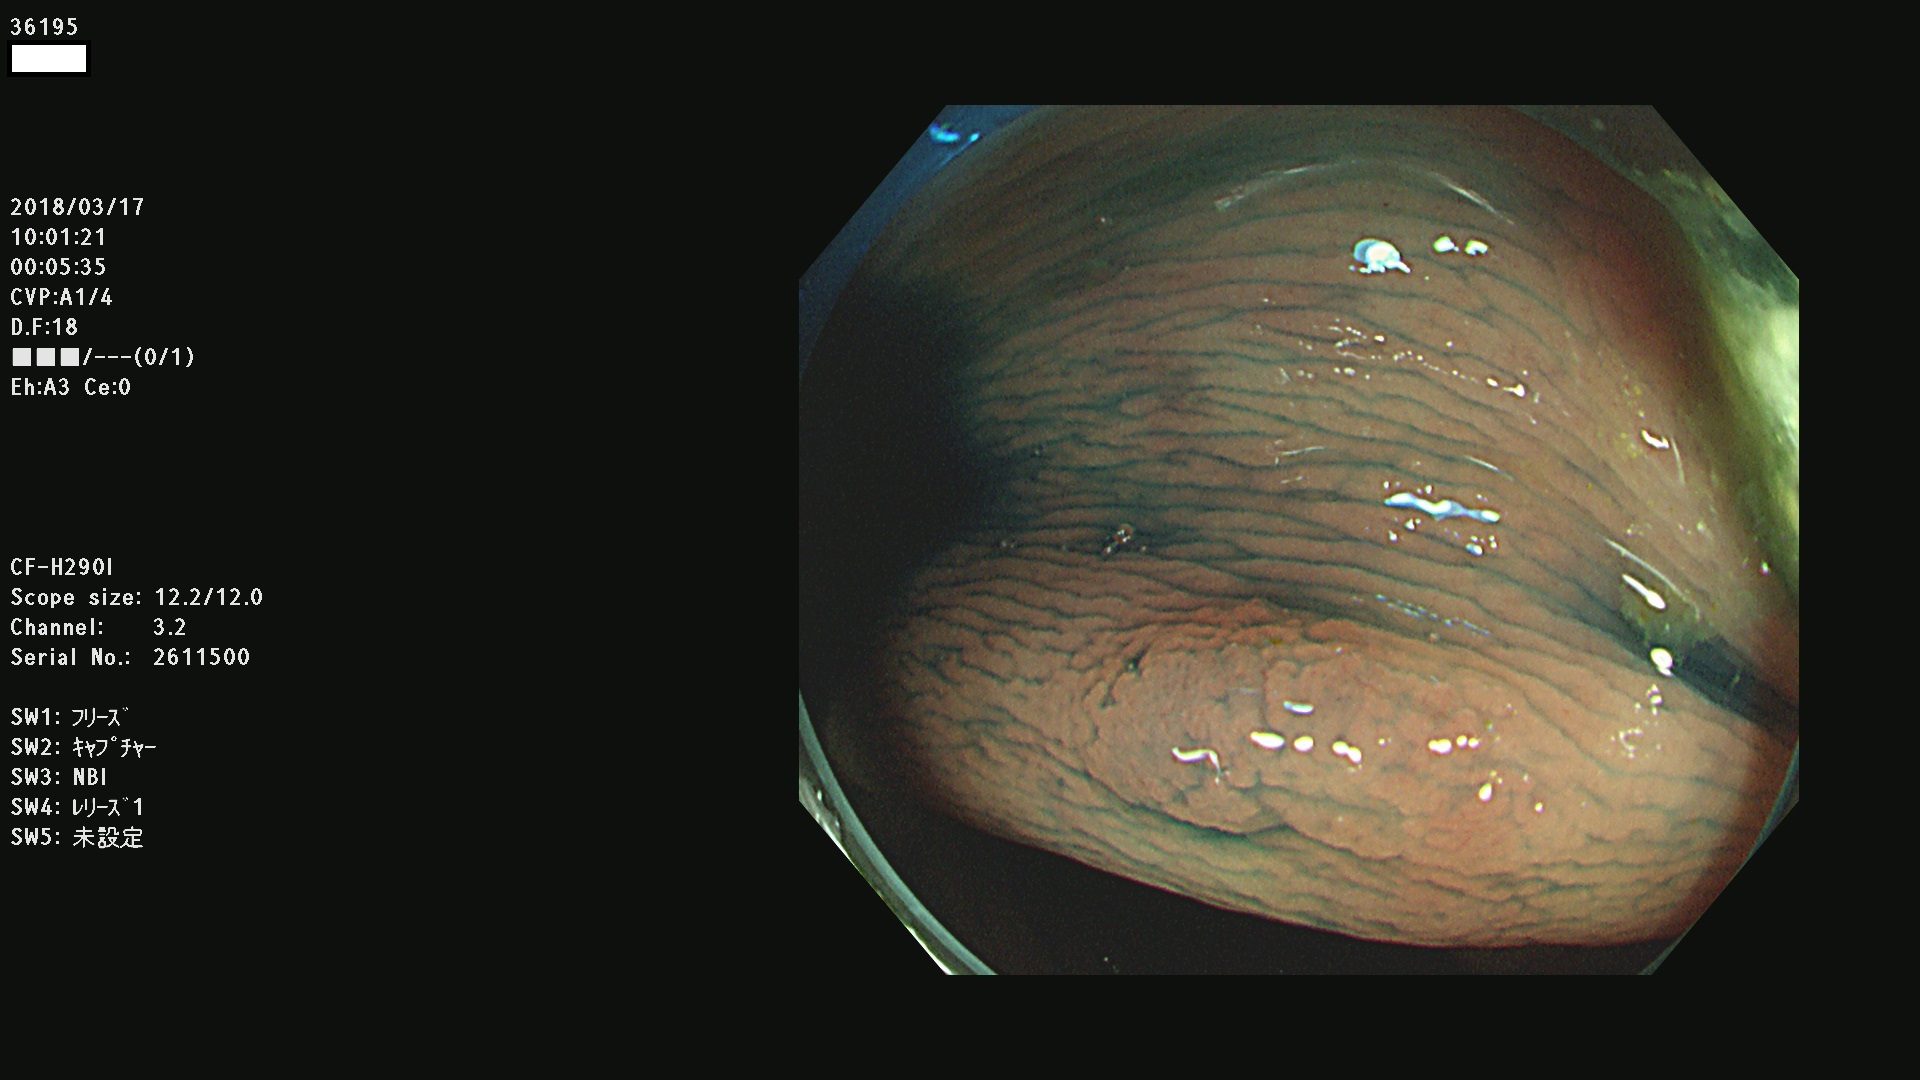

腺腫発見率57 % (カルテ番号 36100〜36199の100名の方の検査結果で集計)大腸癌検診最新情報

以下のカルテ番号の方に腺腫(Adenoma,Group3〜5)が見つかりました(集計法)

36100 36101 36102 36103 36104 36105 36107 36108 36110 36111 36114 36115 36117 36119 36120 36122 36125 36127 36129(SSA/Pのみ) 36133 36135 36137 36138 36139 36143 36144 36146 36147 36152 36153 36154 36155 36157(SSA/Pのみ) 36158 36162 36163 36165 36167 36169 36170 36173 36174 36176 36177 36178 36179 36180 36183 36185 36187 36189 36190(SSA/Pのみ) 36191 36193 36195(SSA/Pのみ) 36197(SSA/Pのみ) 36199(SSA/Pのみ)

発見困難で危険性の高い平坦型病変(上記100名より抽出) ![]()